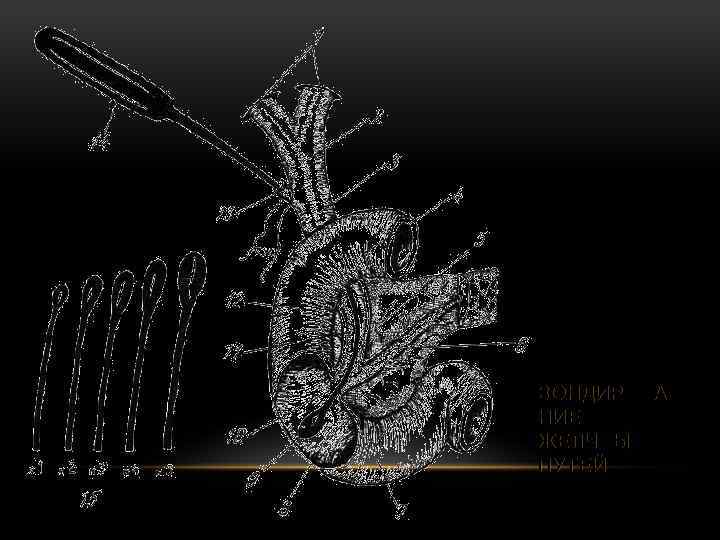

ЗОНДИРОВА НИЕ ЖЕЛЧНЫХ ПУТЕЙ

ЗОНДИРОВА НИЕ ЖЕЛЧНЫХ ПУТЕЙ